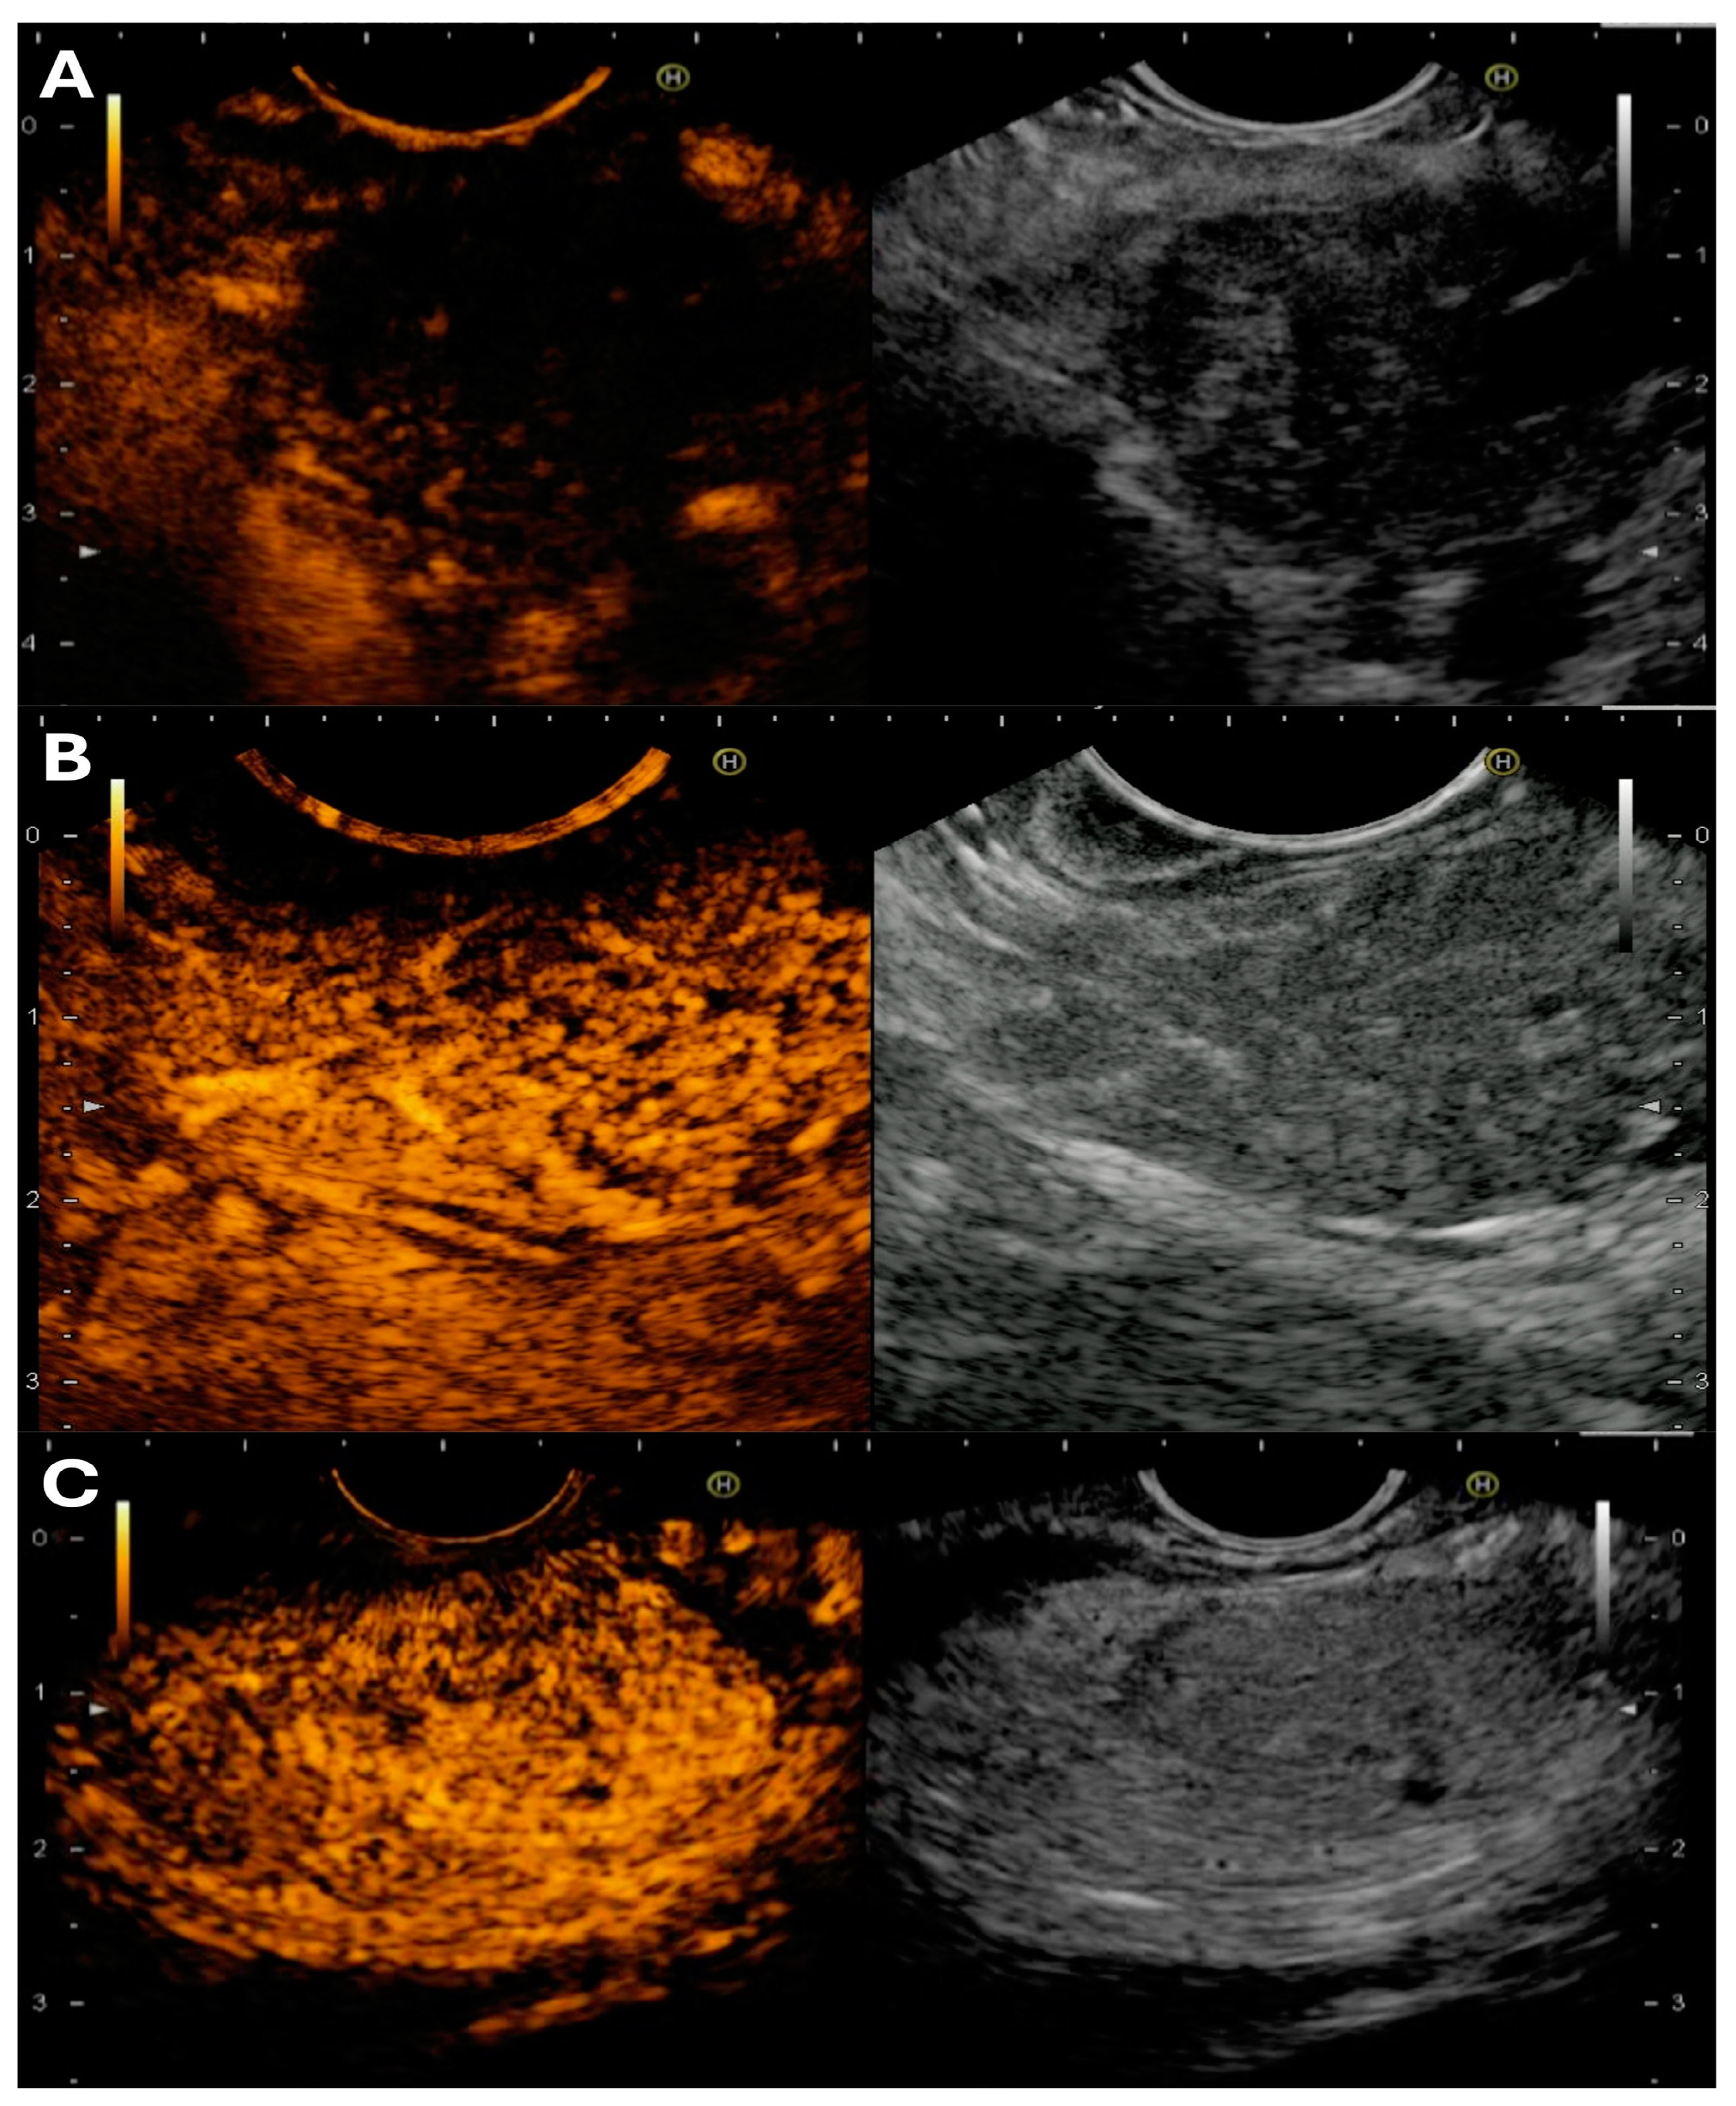

Briefly, the three common differentials of pancreatic lesions show the following properties of CH-EUS and EUS-E [26] (Figure 2):

Figure 2.

Different contrast-enhanced endoscopic ultrasound patterns: (A) hypovascular appearance of pancreatic ductal adenocarcinoma; (B) isovascular focal autoimmune pancreatitis; and (C) a neuroendocrine tumor with hypervascular pattern.